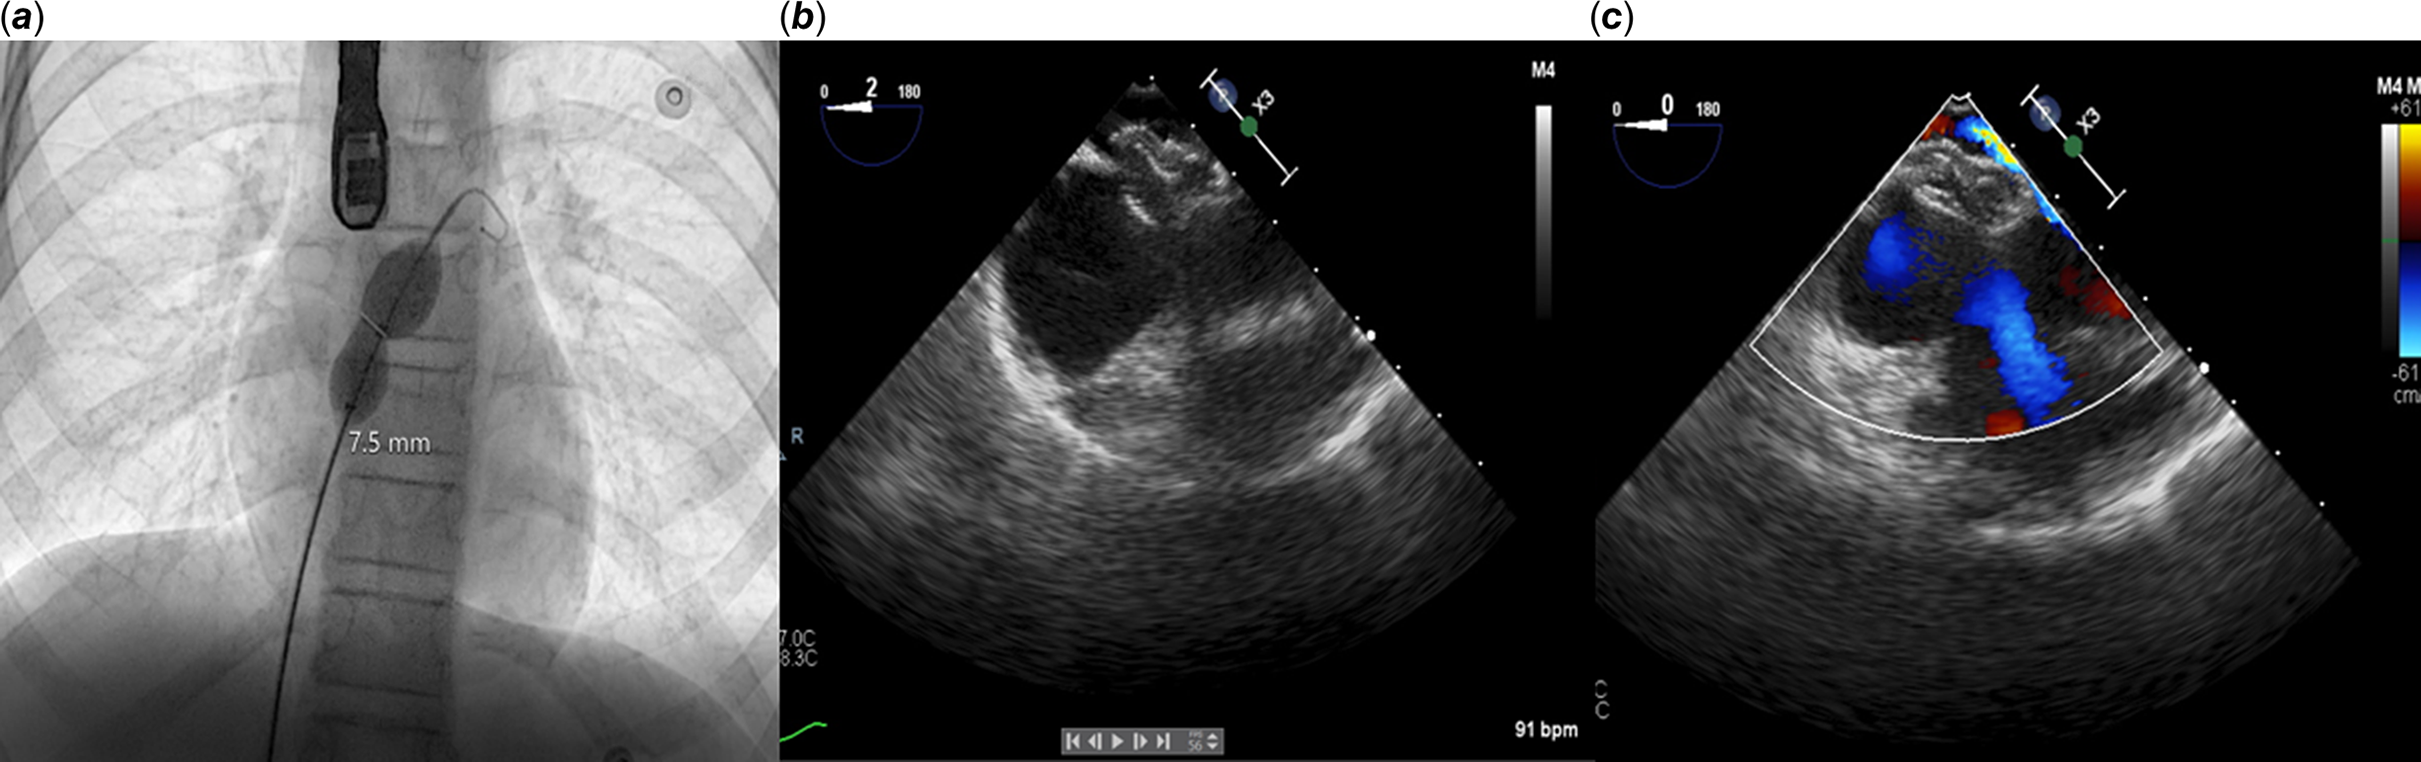

Transesophageal echocardiography and cardiac catheterisation were performed under general anaesthesia. Transesophageal echocardiography revealed a patent foramen ovale tunnel and floppy atrial septum, but without obvious right-to-left shunting in the supine position (Fig 1). Right and left atrium mean pressures were 9 and 11 mmHg, respectively, and pulmonary artery pressure was 25/13, with a mean value of 18 mmHg. No shunt was observed at pulse oximetry. A 0.035-inch guidewire was passed easily through a 5 F vertebral catheter into the left atrium. Patent foramen ovale width via a balloon sizing catheter was 7.5 mm (Fig 2a). The defect was successfully closed using a 9 mm Amplatzer septal occluder (Fig 2b). Control transesophageal echocardiography and contrast injection showed no residual shunt (Fig 2c). The day after transcatheter patent foramen ovale closure, oxygen saturation and partial pressure of arterial oxygen were normal in the upright position and the symptoms disappeared completely. A 6-minute walking test revealed normal oxygen saturation (pre- and post-test saturations were 99% and 98%, respectively). The patient was discharged after 72 hours with 5 mg/kg aspirin therapy. She remains asymptomatic at 6 weeks of follow-up and can perform all daily activities and work without signs of desaturation.

Figure 2. ( a ) The width of the patent foramen ovale (PFO) was measured at 7.5 mm using a balloon sizing catheter. ( b and c ) Control transesophageal echocardiography revealed no residual shunt on the 9 mm Amplatzer septal occluder.